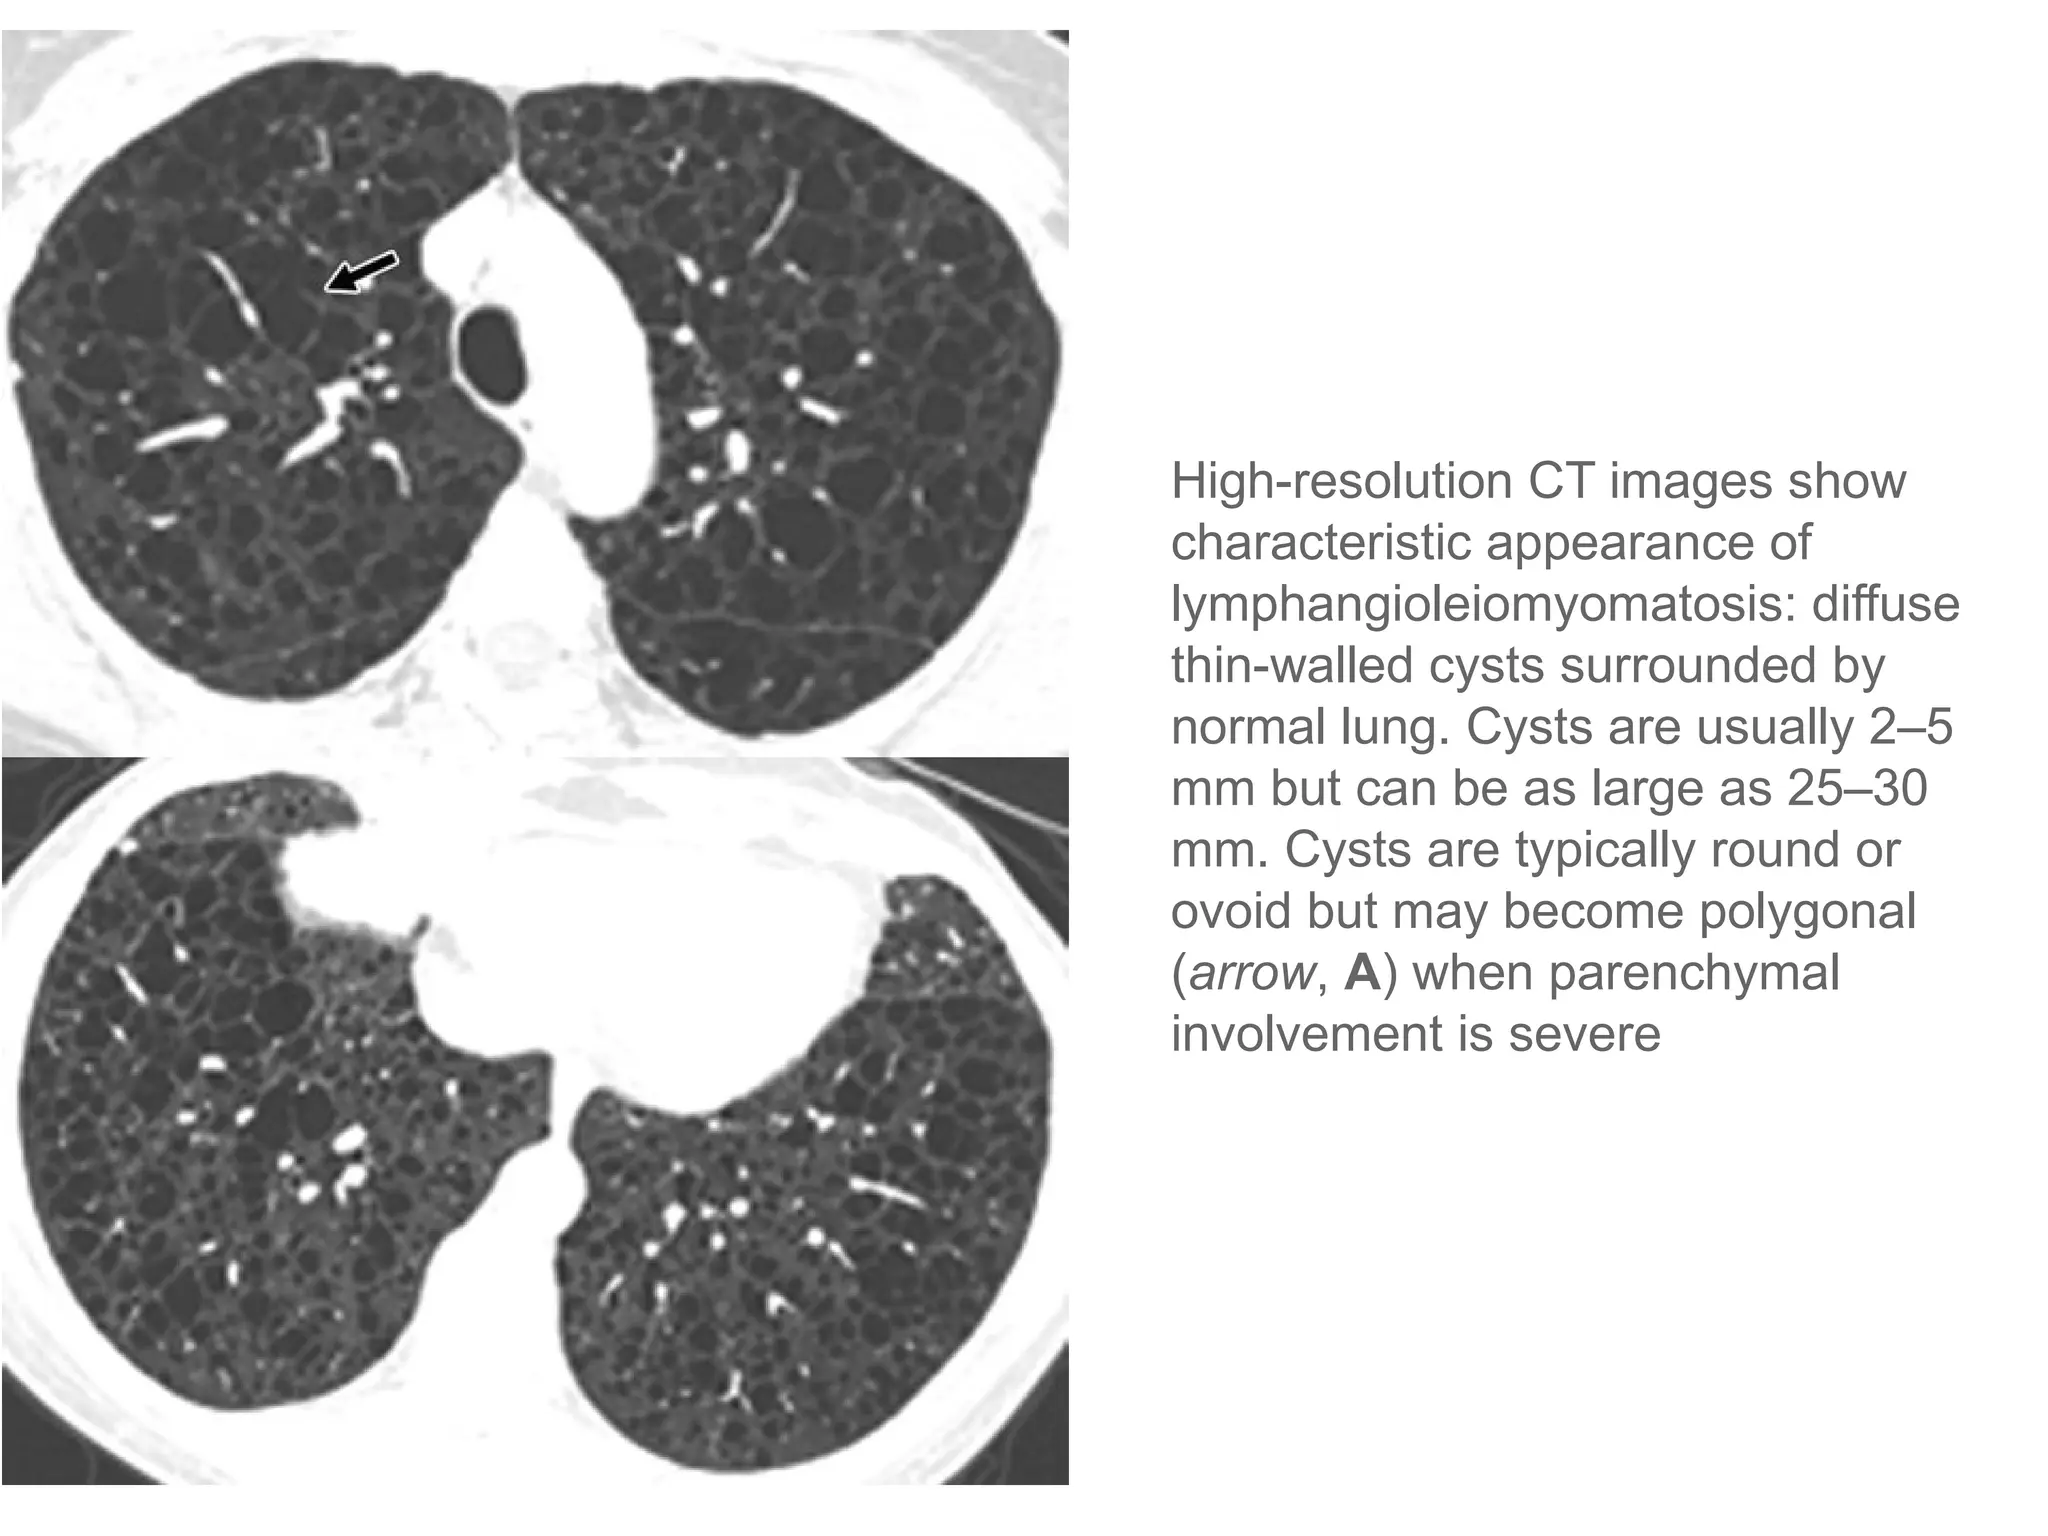

High-resolution CT images show

characteristic appearance of

lymphangioleiomyomatosis: diffuse

thin-walled cysts surrounded by

normal lung. Cysts are usually 2–5

mm but can be as large as 25–30

mm. Cysts are typically round or

ovoid but may become polygonal

(arrow, A) when parenchymal

involvement is severe

High-resolution CT imagesshow characteristic appearance of lymphangioleiomyomatosis: diffuse thin-walled cysts surrounded by normal lung. Cysts are usually 2–5 mm but can be as large as 25–30 mm. Cysts are typically round or ovoid but may become polygonal (arrow, A) when parenchymal involvement is severe